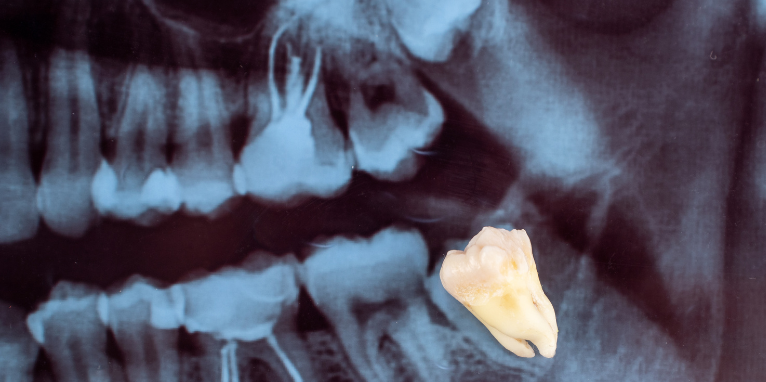

Перед удалением зуба мудрости в нашей клинике обязательно проводится тщательная диагностика. Наши специалисты делают рентгенологическое исследование для оценки положения зуба, количества и формы корней, их отношения к анатомическим структурам. Особенно важно определить расстояние до нижнечелюстного канала при удалении нижних восьмых зубов, так как в канале проходит нервно-сосудистый пучок, повреждение которого может привести к осложнениям.

Мы используем панорамный снимок или прицельный рентген в зависимости от ситуации. На снимке наши врачи оценивают степень ретенции зуба, наклон его оси, состояние окружающей костной ткани, наличие патологических изменений. Эта информация позволяет нам спланировать ход операции, подготовить необходимые инструменты, предупредить пациента о возможной сложности процедуры. В нашей стоматологии мы всегда показываем пациенту снимок и объясняем план удаления.